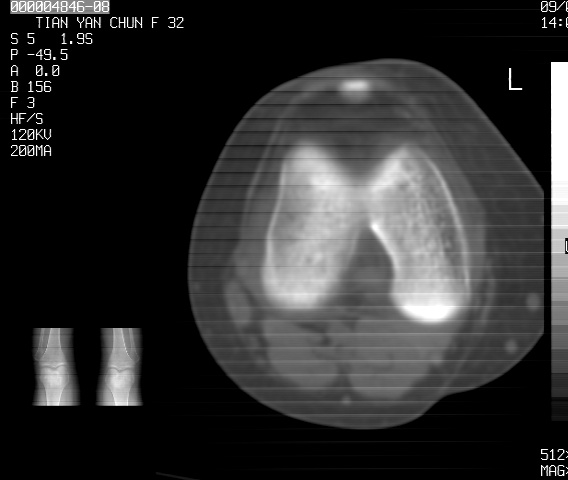

标题: CT18487:请会诊,女32岁,左膝疼痛数日 [打印本页]

标题: CT18487:请会诊,女32岁,左膝疼痛数日

关节面软骨有硬化环考虑退行性变

定位片可见髁间棘骨质增生,支持膝关节退行性变。

定位片可见髁间棘骨质增生,支持膝关节退行性变。建议mri 检查

考虑骨性关节炎